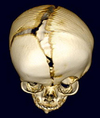

A 3-year-old boy is brought for evaluation of a right frontotemporal cranial defect. A photograph is shown. Which of the following materials is most appropriate for reconstruction?

The correct response is Option A.

Autologous bone is the most appropriate material for inlay cranioplasty for a child this age. Each of the other options has been used in the pediatric population, but they carry important limitations. Porous polyethylene can be used to reconstruct large cranial defects, but is expensive to fabricate, has the potential to become unstable in a growing cranium, and has a higher overall infection rate than autologous bone. Bone morphogenetic protein (BMP) has shown promise in animal models for inducing bone formation in large cranial defects, but it is expensive for a defect of this size; it is a powerful mitogen and can result in dural ossification and, potentially, induction of tumor growth. Calcium phosphate pastes also have been advocated but are very expensive and for a defect of this size, the long-term potential osseointegration is dubious. Furthermore, the risk of infection and/or implant extrusion is higher. Titanium mesh may be appropriate for some children with limited life expectancy or functional needs, but these implants can be bent, offer limited impact resistance, and have a higher overall rate of complications than autologous bone.